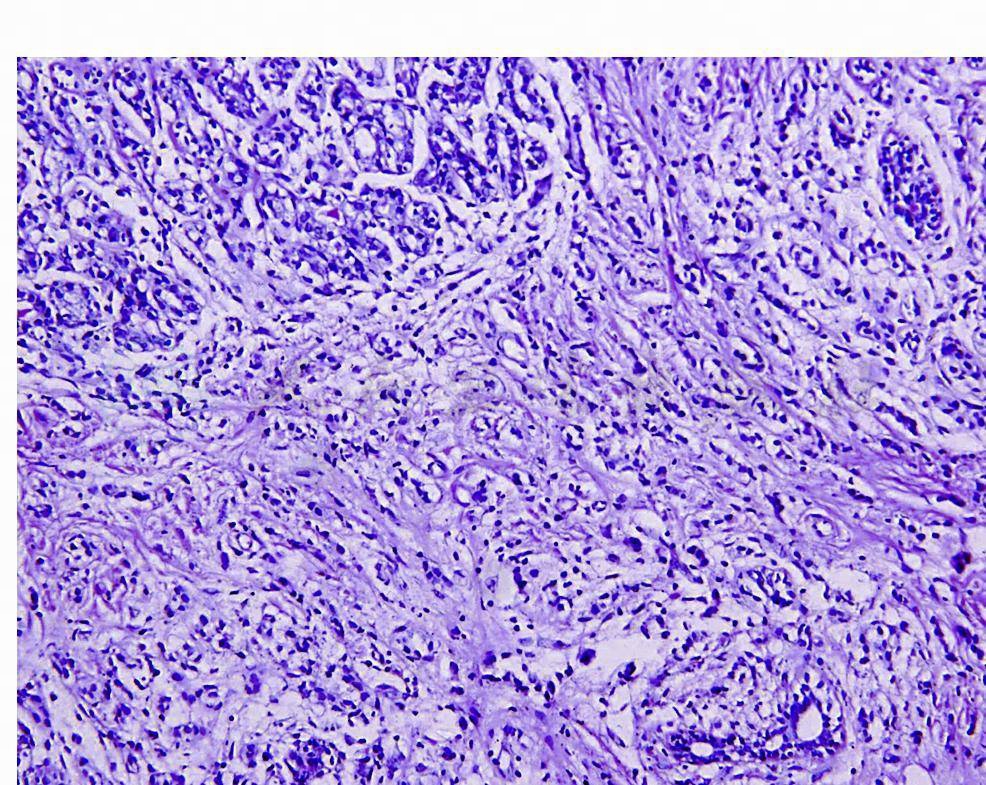

(一)腺泡型

浸润癌细胞排列成腺泡状,腺泡由数十个细胞呈球状聚集在一起,之间被纤维间质束分割,其形态与小叶原位癌相似,但缺乏肌上皮细胞和基底膜包绕,有时腺泡周围可见不规则的黏液样细胞,癌细胞通常类似于经典型细胞,小‐中等大小,较均匀一致,胞质可淡染‐透明状(图1,图2)。

图1 浸润性小叶癌(腺泡型)

图2

腺泡周围有纤细的间质,癌细胞和经典型类似,胞质透明